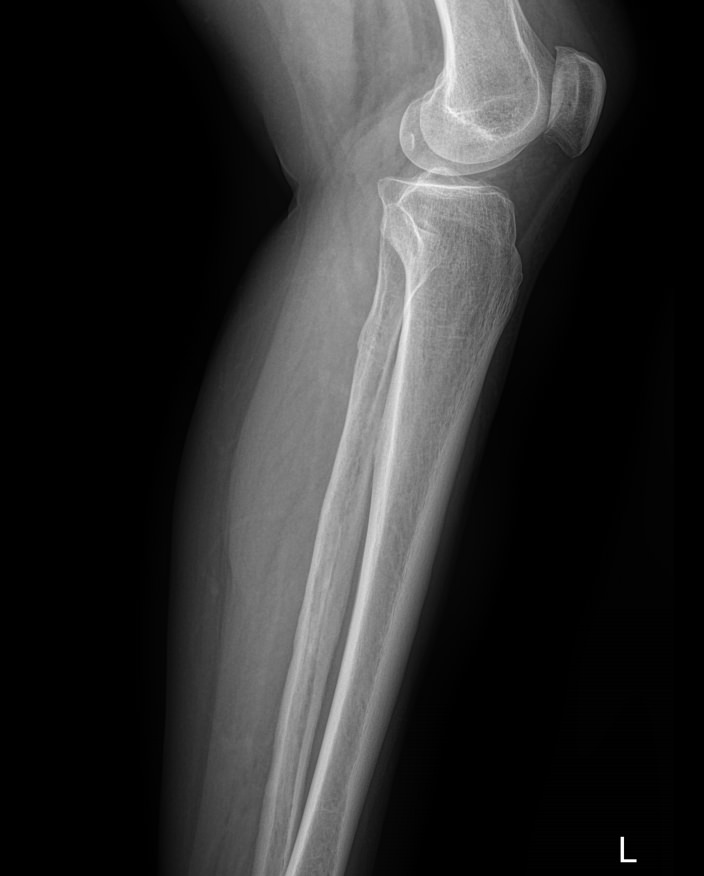

В области голени располагаются 2 кости ― большая и малая берцовые. Разные по толщине, они, тем не менее, составляют крепкую конструкцию, позволяющую человеку ходить и бегать, нести вес тела и дополнительный груз. Повреждение и травмы голени, а также прилежащих суставов, коленного и голеностопного, резко уменьшает мобильность человека. Хронические процессы, начинаясь незаметно, постепенно приводят к тому же.

Рентген является простым, доступным, высокоинформативным и безболезненным видом диагностики патологий костной ткани, в том числе ― костей голени. А современная цифровая аппаратура позволяет выполнять снимки настолько часто, насколько этого требует заболевание, не превышая допустимую дозу облучения.

На снимке рентгенолог последовательно просматривает все образования голени и описывает их изменения:

• Новообразования: местоположения, затрагивают ли костную ткань;

• Диафизы и эпифизы костей: наличие перелома, его смещения, костной мозоли, их месторасположение и соответствие срокам травмы;

• Костная ткань: очаги разрежения, уплотнения, размягчения, склерозирования и других изменений, в том числе послеоперационных;

• Надкостница: истончение, обызвествление;

• Входящий в снимок сустав: есть ли изменения, типичные для травмы или воспаления;

• Мягкие ткани: есть ли отек и инородные тела.

Специальная подготовка не нужна. Пациент снимает одежду с нижней половины туловища, оставаясь в белье, надевает защитную накидку, и ложится на снимочный стол, как показывает рентгенолаборант. Обычно снимок делают в прямой проекции, то есть нога лежит прямо. Но если в направлении врач указывает боковую проекцию, пациент ложится на бок, а исследуемую ногу немного сгибает. В обоих случаях здоровая нога отводится в сторону. Также в направлении указывается, какой сустав должен войти в снимок ― коленный или голеностопный.